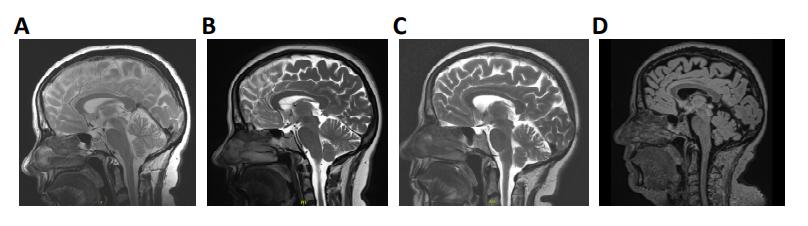

Figure 1. A heterozygous KCNC3 variant in an atypical case of SCA13 with a dominant central rotational vertigo, only mild progressive cerebellar symptoms and an early onset of cognitive impairment. (A) Mid-sagittal T1/T2 and Flair-sequence MR image of the patient in 2024 showing a mild cerebellar atrophy and (B) a global reduction of brain volume. (C) Topology of a Kv3.3 channel subunit. The location of the E675K variant is highlighted in purple and the location of the alternative start of the N-terminus is highlighted in turquoise. (D) Partial amino acid sequence alignment of different Kv3.3 orthologues. The conserved E675 residue is highlighted in purple. |

Supplementary Figure 1. Mid-sagittal T1/T2 and Flair-sequence MR images. Images were taken in

(A) 2010, (B) 2014, (C) 2019, and (D) 2024, respectively. |